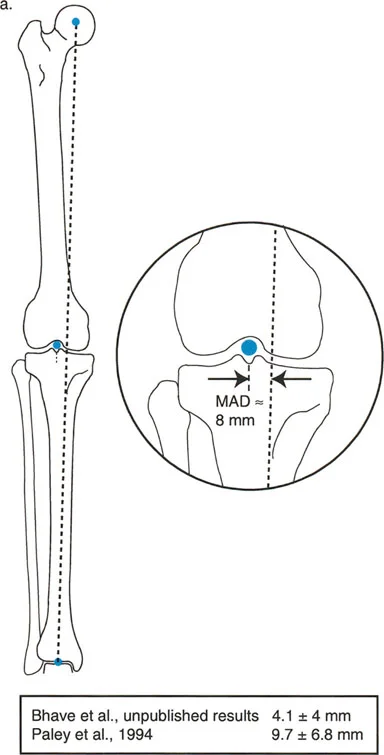

Frontal Plane Femoral Angles

- mLDFA (mechanical Lateral Distal Femoral Angle): The angle between the mechanical axis of the femur and the distal femoral joint line on the lateral side.

- Normal Value: 87° (Range: 85° - 90°)

- aLDFA (anatomic Lateral Distal Femoral Angle): The angle between the anatomic axis of the femur and the distal femoral joint line on the lateral side.

- Normal Value: 81° (Range: 79° - 83°)

Frontal Plane Tibial Angles

Because the mechanical and anatomic axes of the tibia are parallel, we generally refer only to the mechanical angles, which apply to both axes.

- MPTA (Medial Proximal Tibial Angle): The angle between the mechanical/anatomic axis of the tibia and the proximal tibial joint line on the medial side.

- Normal Value: 87° (Range: 85° - 90°)

Step 2 The Malorientation Test

If the MAD is abnormal, you must identify the source. Measure the mLDFA, MPTA, and JLCA.

* Femoral Origin: If the mLDFA is abnormal but the MPTA is normal, the deformity is in the femur.

* Tibial Origin: If the MPTA is abnormal but the mLDFA is normal, the deformity is in the tibia.

* Combined Origin: If both are abnormal, a double-level osteotomy may be required.